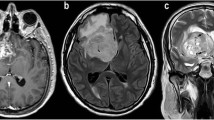

Regarding rCBVt value, for high-grade glioma (Fig. 1), the mean was 3.5 (1.8–6.13), and for low-grade glioma (Fig. 2) 1.16 (0.5–1.7) (P = 0.0001). There is statistical significance for differentiation between low- and high-grade glioma (Fig. 3) (shown in Table 2).

A 30-year-old male presented by amnesia, slurred speech and right hemiparesis since 1 month. a Axial T2 showing left tempero-parietal large ill-defined SOL surrounded by moderate vasogenic edema. b T1 post Gd showing faint heterogeneous enhancement. c Intermediate echo spectroscopy curve shows Cho/Cr ratio 3.5, Cho/NAA ratio 6, and elevated lactate and lipid peaks. d Perfusion-weighted images PWI and rCBV color perfusion map for the lesion show marked signal drop of the lesion and area of relative hyper-perfusion rCBV5.8, and for the perilesional edema show no signal drop and area of subtle hyper-perfusion rCBV 1.2. Collectively, the findings are in favor of HGG. Histopathological examination confirmed the diagnosis: diffuse anaplastic astrocytoma WHO GRADE III

A 26-year-old female presented by gradual behavior changes and right hemiparesis for 2 months. a Axial T2WI showing a large rather defined mass in left frontotemporal showing hyperintense signal, surrounded by mild vasogenic edema. b Axial T1 post Gd showing no enhancement. c Intermediate echo spectroscopy curve shows Cho/Cr ratio 1.5 and Cho/NAA ratio 1.8. d Perfusion-weighted images PWI and rCBV color perfusion map for the lesion and edema show a mild signal drop of the lesion and area of relative hyper-perfusion rCBV 1.5, also for edema rCBV 0.7. Collectively, the findings are in favor of LGG. Histopathological examination confirmed the diagnosis: diffuse astrocytoma WHO GRADE II